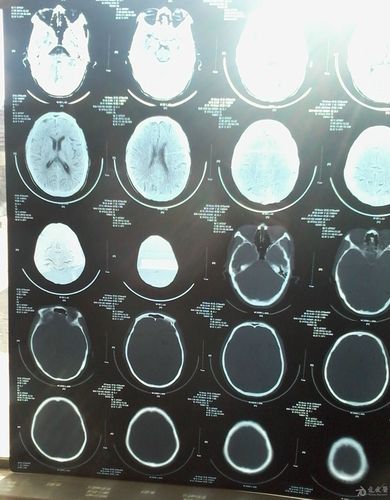

脑萎缩ct

脑萎缩图片

脑萎缩ct表现

脑萎缩ct图片

脑萎缩的ct表现及图解

脑萎缩ct片子图片

脑萎缩ct图片解说